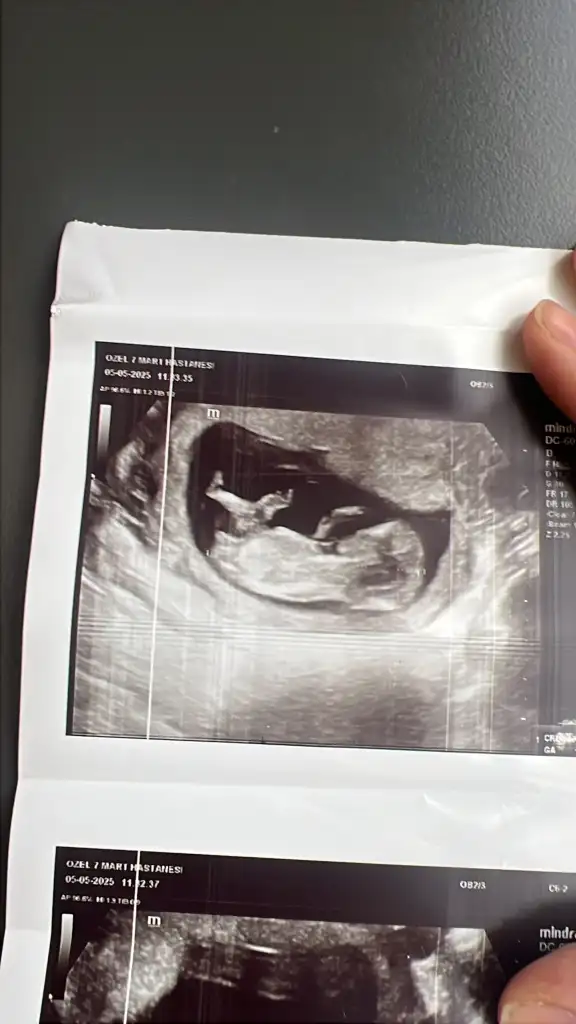

Kızlar lütfen yorum yapar mısınız 15 haftalığz

Benim bebegime de bakar misiniz 16 haftalik görüntüsüBilemedim inanınbelki bilen biri görür yorum yapar sizin için

Merhaba ilk önce rabbim hayırlısını ve gönlünüze göre olanı versin inşallah nub teoremine göre sanki kız gibi

Merhaba erkek gibi duruyorEki Görüntüle 3587975

Merhabalar erkek gibi duruyor ama nubda tam aci tam yukari degil hafif yukari skull teorisine gorede erkek gibi duruyor ama tab i Rabbim gonlunuze gore versin insallah tahminim bu Allah bilir gerisini saygilarEki Görüntüle 3587975